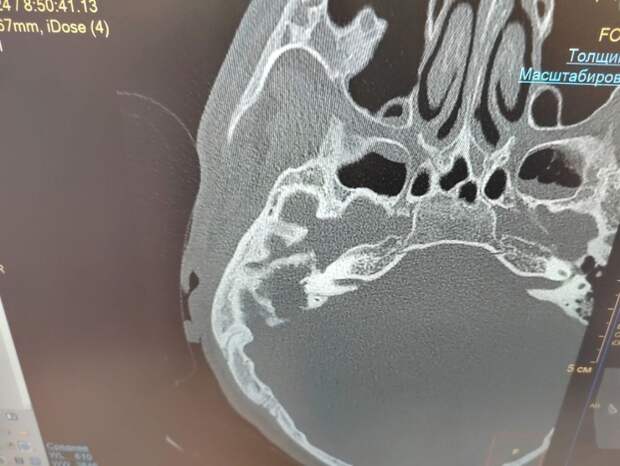

В оториноларингологическом отделении Воронежской областной детской клинической больницы №1 вылечили 17-летнего пациента с правосторонним хроническим гнойным средним отитом, осложненным холестеатомой, фистулами горизонтального и вертикального полукружных каналов, лабиринтитом. Об этом рассказали на официальной страницы ВОДКБ № 1 «ВКонтакте». Пациент обратился к врачу с жалобами на головокружение, потерю равновесия и гнойные выделения из правого уха в течение 4 дней. Ранее подобные выделения наблюдались у юноши в течение нескольких лет. Пациента госпитализировали в оториноларингологическое отделение больницы. После проведения компьютерной томографии височных костей были выявлены признаки холестеатомы полостей среднего уха с признаками деструкции костной стенки и другими патологическими изменениями.

Как рассказали в ВОДКБ № 1, холестеатома - это измененная кожа, проникнувшая в полость среднего уха, где ее быть не должно быть. Кожа постоянно обновляется, как ей и положено. Но, поскольку она оказалась в неположенном месте, продукты ее жизнедеятельности скопились и начали разрушать окружающие ткани. В срочном порядке, контролируя процесс с помощью операционного микроскопа, врачи проведели санирующую операцию на правом ухе.

Хирургия холестеатомы - сложнейшее вмешательство на среднем ухе, требующее от хирурга высочайшей техники и опыта. Образование удалили из полостей среднего уха и провели пластика костных дефектов надхрящницей и костной стружкой. Хронический гнойный средний отит нередкая патология в детской оториноларингологической практике, однако деструкция костной стенки сигмовидного синуса и крыши антральной полости были прямым путем развития более тяжелого внутричерепного осложнения, что требовало срочного хирургического вмешательства. Хирурги оториноларингологического отделения ВОДКБ №1 впервые столкнулись с наличием таких патологий у одного пациента. Мальчика выписали на 10 день после операции с выздоровлением.